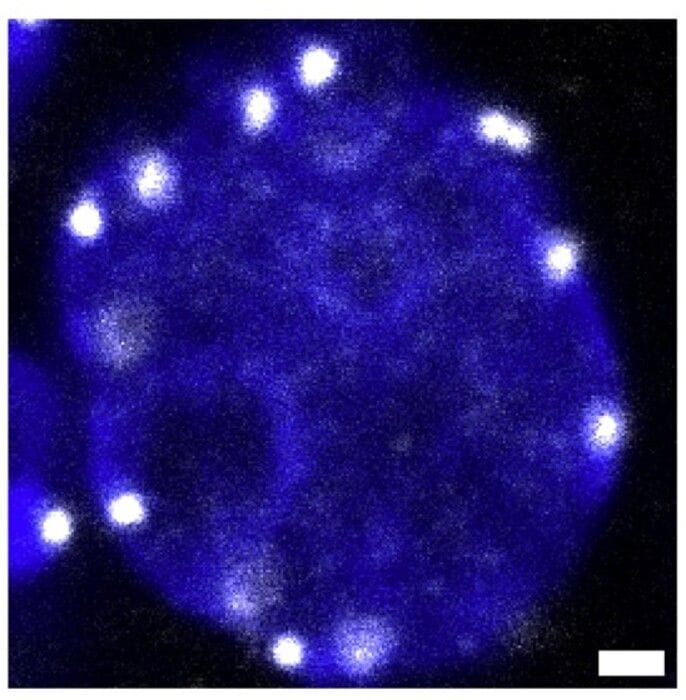

I risultati dimostrano che nel momento in cui la cellula germinale embrionale è pronta ad affrontare la meiosi (la divisione che dimezza il patrimonio genetico per generare i gameti, ovuli o spermatozoi), il centromero dei cromosomi, ovvero la struttura al centro dei loro quattro bracci , si sposta ai margini del nucleo della cellula e la struttura tridimensionale del Dna si 'rilassa'. Questo riposizionamento sembra fondamentale per la preparazione alla meiosi e non è mai stato riscontrato nei modelli cellulari coltivati in vitro , un possibile indizio sul perché sia così difficile replicare questo processo in laboratorio.